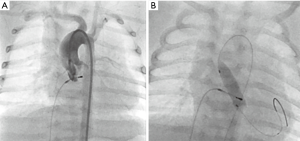

Newborns with critical aortic coarctation, associated myocardial failure and no response to prostaglandin can be effectively palliated by balloon angioplasty; it seems to be the method of choice as bridging procedure to corrective surgery (Figure 4A,B,C,D). Without describing the technique in detail, after angiographic delineation of the lesion, diameters of the transverse aortic arch, the descending aorta and minimum diameter of the coarctation are measured and a high-pressure balloon is chosen with a diameter not exceeding the diameter of the transverse arch or of the descending aorta at diaphragm level. Repetitive angioplasties with different balloons may be required. After angioplasty, angiography and hemodynamic measurements should be repeated. Considering the high re-stenosis rate in neonates, balloon angioplasty is only a palliation and serve as bridge-to-surgery procedure (30,31).